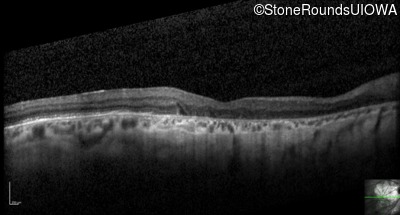

Optical Coherence Tomography - Left - 20/200

Exemplar / OCT Stack